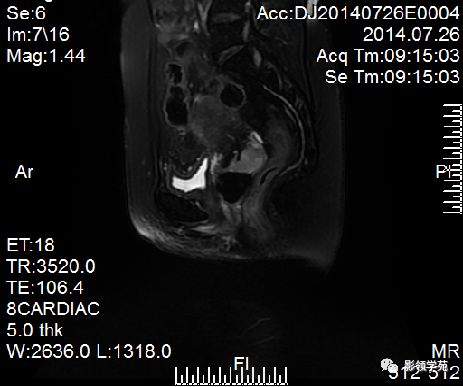

Ⅰ期

IIA期

IIB期